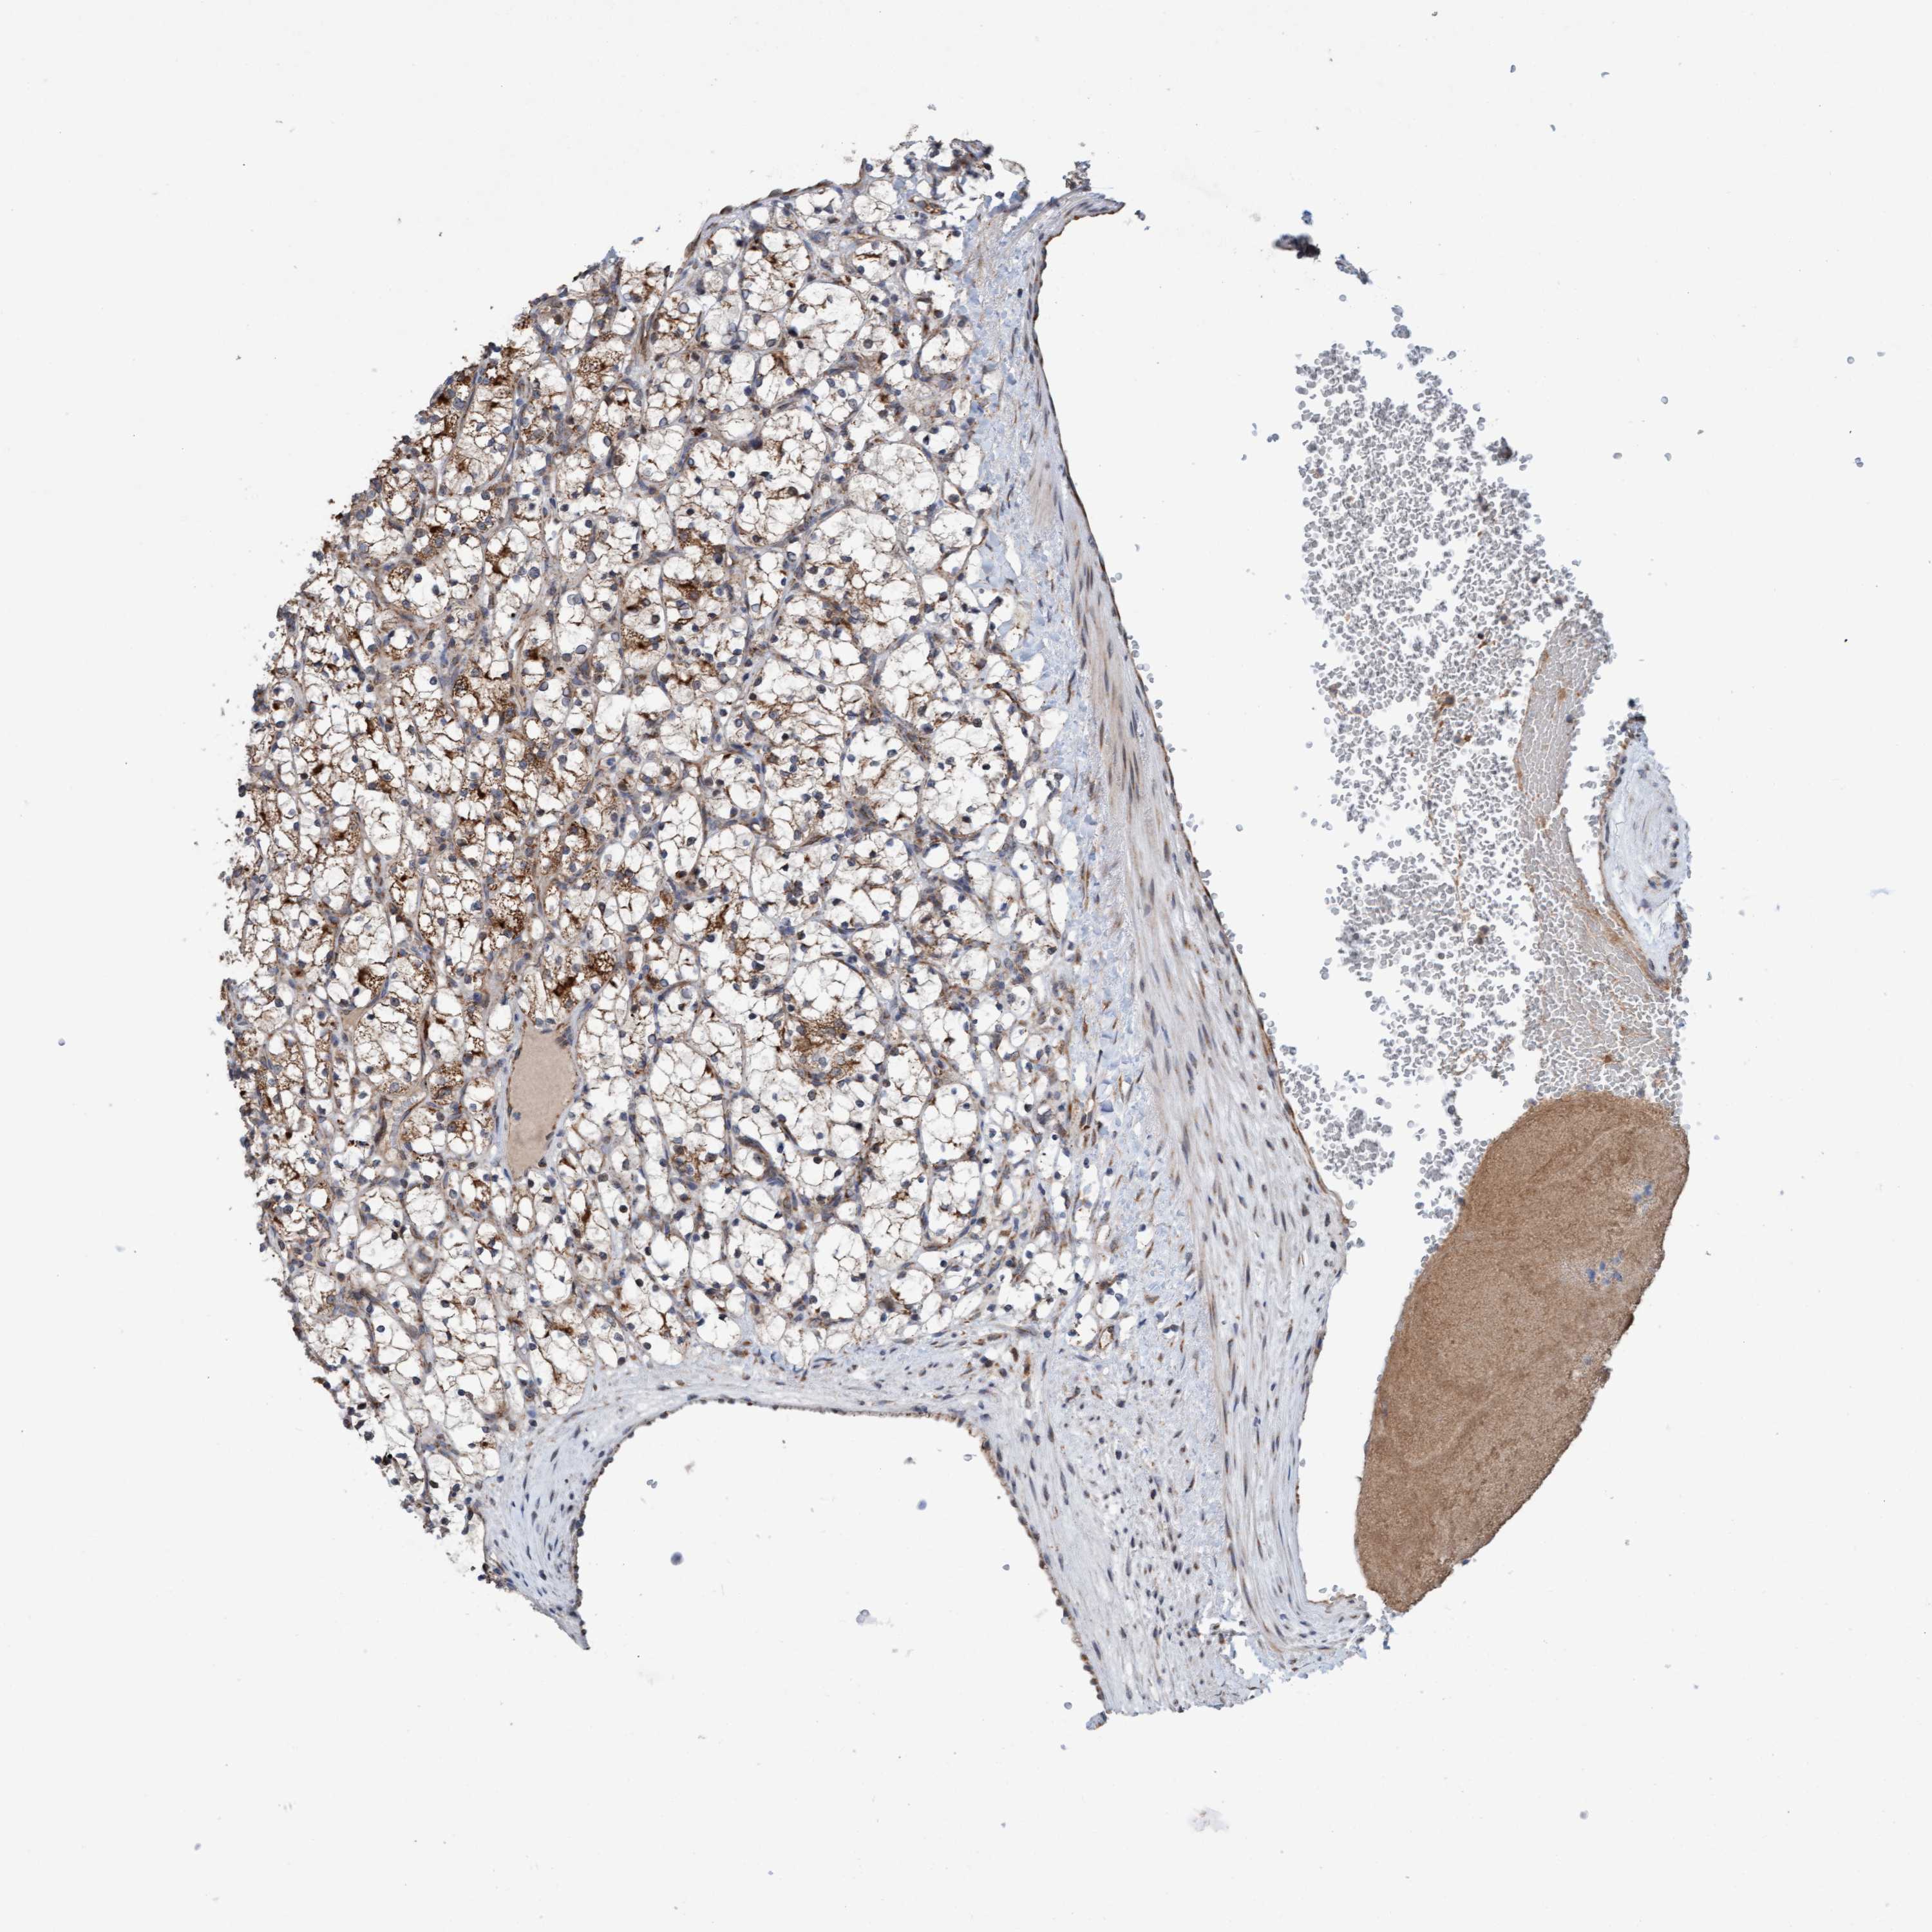

KIDNEY RENAL CLEAR CELL CARCINOMA (VALIDATION) - Interactive survival scatter ploti

The Survival Scatter plot shows the clinical status (i.e. dead or alive) for all individuals in the patient cohort, based on the same data that underlies the corresponding Kaplan-Meier plots. Patients that are alive at last time for follow-up are shown in blue and patients who have died during the study are shown in red.

The x-axis shows the expression levels (FPKM) of the investigated gene in the tumor tissue at the time of diagnosis. The y-axis shows the follow-up time after diagnosis (years). Both axes are complimented with kernel density curves demonstrating the data density over the axes. The top density plot shows the expression levels (FPKM) distribution among dead (red) and alive patients (blue). The right density plot shows the data density of the survived years of dead patients with high and low expression levels respectively, stratified using the cutoff indicated by the vertical dashed line through the Survival Scatter plot. This cutoff is automatically defined based on the FPKM cutoff that minimizes the p-score. The cutoff can be changed by dragging the vertical line or by entering a cutoff value in the square labeled "Current cut-off".

Under the Survival Scatter plot the p-score landscape (black curve; left axis) is shown together with dead median separation (red curve; right axis). Dead median separation is the difference in median mRNA expression between patients who have died with high and low expression, respectively. It is calculated as follows: median FPKM expression of dead patients with high expression - median FPKM expression of dead patients with low expression. This is intended to aid the user in visually exploring custom cutoffs and the associated p-scores and dead median separation.

Individual patient data is displayed and can be filtered by clicking on one or more of the category buttons on the top of the page. Categories describing expression level and patient information include: high, low, alive, dead, female, male and tumor stages. The scale of the x-axis can be toggled between linear and log-scale by clicking on the "x log" button. Mouse-over function shows TCGA ID, patient information and mRNA expression (FPKM) for each patient.

& Survival analysisi

Kaplan-Meier plots summarize results from analysis of correlation between mRNA expression level and patient survival. Patients were divided based on level of expression into one of the two groups "low" (under cut off) or "high" (over cut off). X-axis shows time for survival (years) and y-axis shows the probability of survival, where 1.0 corresponds to 100 percent.

ZNF566 is not prognostic in Kidney Renal Clear Cell Carcinoma (validation)

Best expression cut offi

Based on the FPKM value of each gene, patients were classified into two groups and association between prognosis (survival) and gene expression (FPKM) was examined. The best expression cut-off refers the FPKM value that yields maximal difference with regard to survival between the two groups at the lowest log-rank P-value. Best expression cut-off was selected based on survival analysis .

When clicking on this number, the vertical dashed line indicating cut-off, the interactive survival plot, and the Kaplan-Meier curve will be adjusted to show results based on the best expression cut-off.

: 4.62

Median expressioni

Median expression refers to the median FPKM value calculated based on the gene expression (FPKM) data from all patients in this dataset. When clicking on this number, the vertical dashed line indicating cut-off, the interactive survival plot, and the Kaplan-Meier curve will be adjusted to show results based on the median expression.

: N/A

Median follow up timei

Median follow up time refers to the median time (years) after diagnosis with this type of cancer, based on clinical data from all patients in this dataset.

P scorei

Log-rank P value for Kaplan-Meier plot showing results from analysis of correlation between mRNA expression level and patient survival.

N/A

5-year survival highi

5-year survival for patients with higher expression than the expression cutoff.

For melanoma and glioma, 3-year survival is shown.

5-year survival lowi

5-year survival for patients with lower expression than the expression cutoff.

TCGA RNA samplesi

RNA-seq data is reported as average FPKM (number Fragments Per Kilobase of exon per Million reads), generated by the The Cancer Genome Atlas (TCGA) .

Normal distribution across the dataset is visualized with box plots, shown as median and 25th and 75th percentiles. Points are displayed as outliers if they are above or below 1.5 times the interquartile range. FPKM values of the individual samples are presented next to the box plot.

Average pTPM 5.2

Number of samples 100